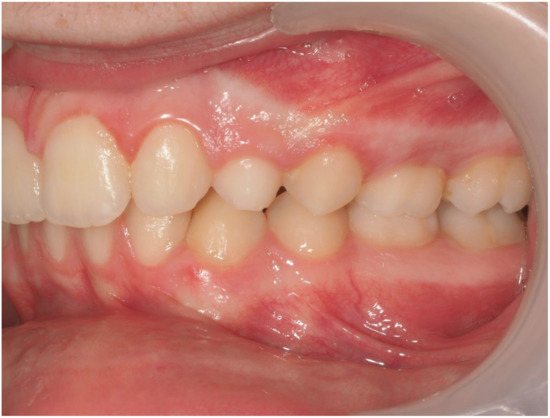

Ultimately, after 30 months of treatment, canine 23 was successfully repositioned into the dental arch, achieving functional occlusion (Figure 23).

Figure 23.

Canine 23 properly positioned in the arch in occlusion; 30 months of treatment.